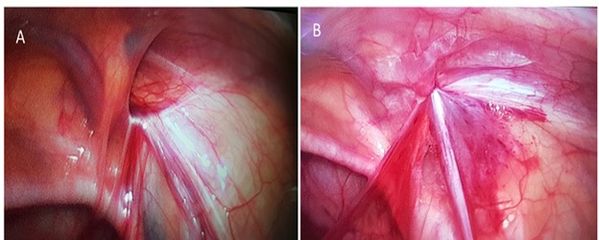

Thoát vị bẹn

Hình ảnh lỗ thoát vị bẹn trước (A) và sau (B) đóng với phẫu thuật nội soi 1 lỗ.

Có nhiều phương pháp mổ nội soi đang được áp dụng tại Việt Nam: Phẫu thuật nội soi 3 lỗ; phẫu thuật nội soi 2 lỗ, phẫu thuật nội soi 1 lỗ.

Cho đến nay thì phẫu thuật nội soi 1 lỗ là phương pháp tốt nhất để điều trị thoát vị bẹn ở trẻ em. Phương pháp này chỉ sử dụng 1 vết mổ nhỏ tại rốn, sau phẫu thuật trẻ đau rất ít, và không để lại sẹo sau mổ.